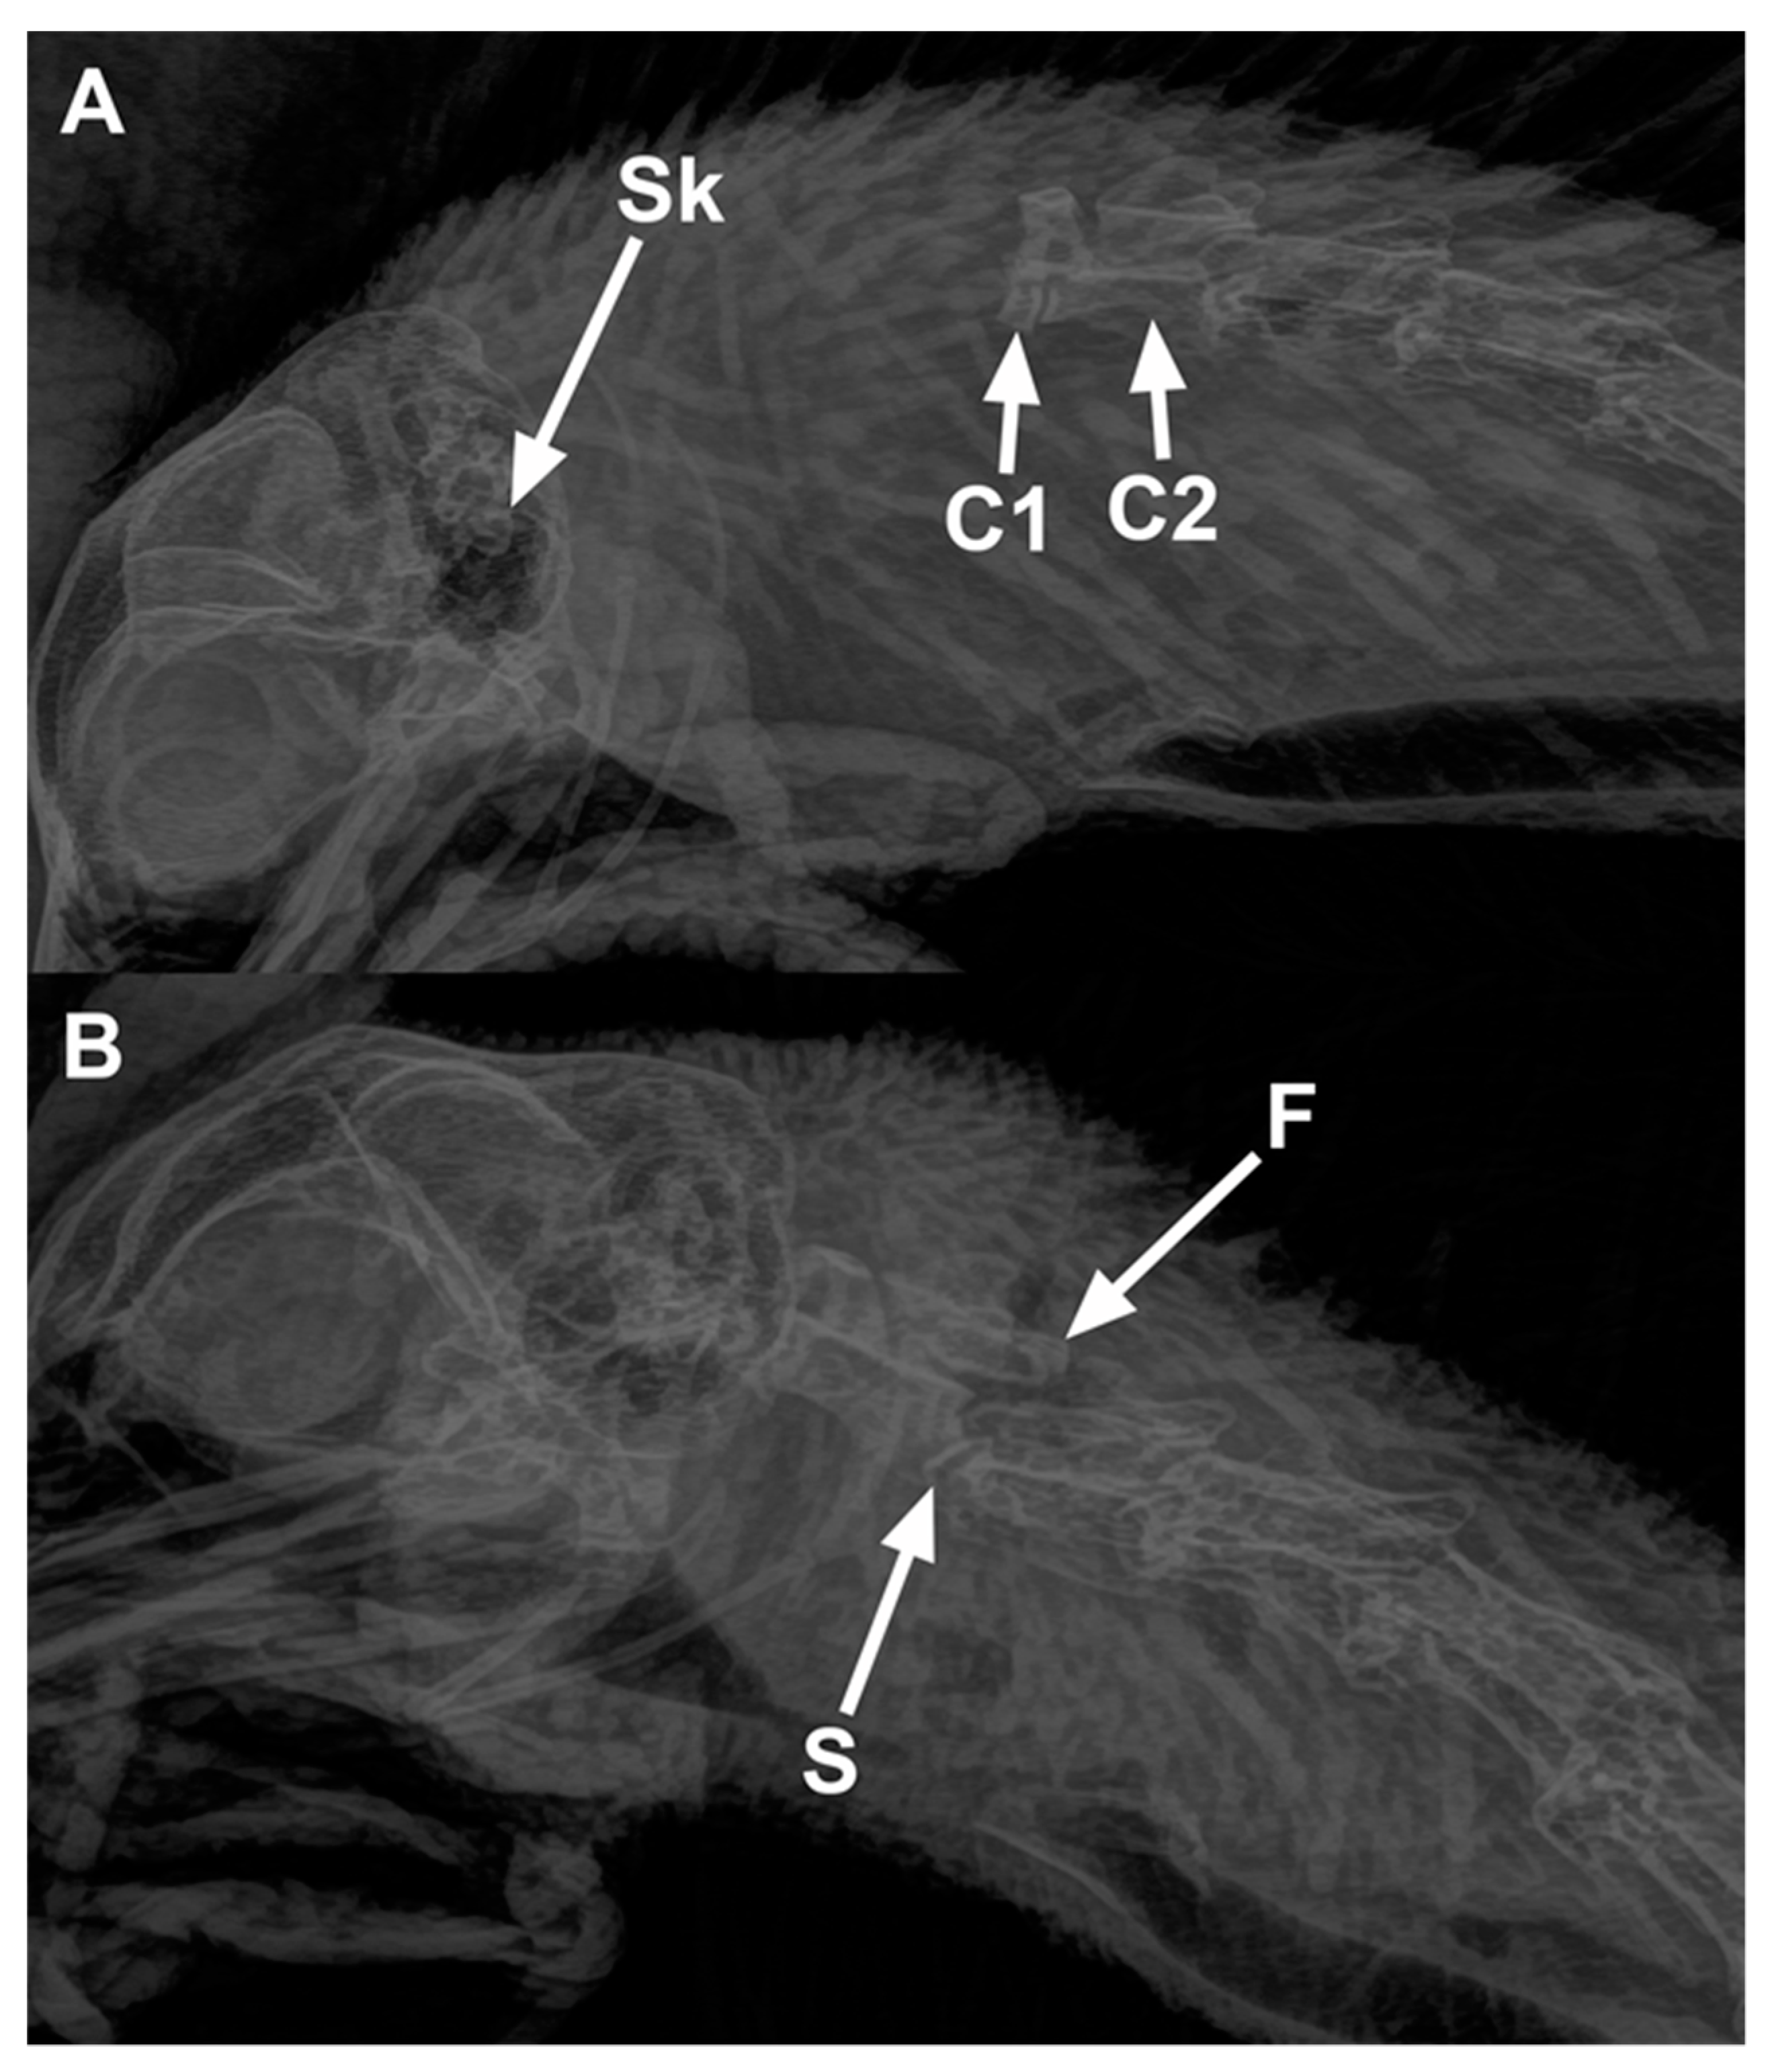

The number of birds scored with fractures and the different types of fractures observed in the cervical vertebrae are presented in Table 9. Fractures were observed in less than 10% of the birds regardless of treatment or whether they presented with luxation or subluxation. There was no difference between manual cervical dislocation and MCD in birds with fractures (p = 0.19). Overall, 4 birds out of 24 (17%) killed with MCD and 3 out of 48 (6%) killed by manual cervical dislocation had fractures of the cervical vertebrae. Radiographs demonstrating cervical dislocations (A—cervical luxation, B—cervical subluxation with a fracture) in a chicken are shown in Figure 2.

Figure 2.

Radiographs of chickens showing cervical dislocations. (A) Luxation between the skull and C1 vertebra in a 65-week-old rooster killed by manual cervical dislocation: Sk—Skull, C1—first cervical vertebra, and C2—second cervical vertebra. (B) Subluxation between C2 and C3 (letter S shows the site of subluxation) in a 65-week-old rooster killed by KED: fractures (F) are present on the articular processes of the C3 vertebra.

Results of radiographic scoring for the presence and site of cervical dislocation are tabulated in Table 8. The cervical vertebrae were assessed for any sites of luxation and/or subluxation. All birds killed by manual CD had luxation (complete dislocation) irrespective of whether they were conscious or anesthetized, whereas only 54% of birds killed by mechanical CD had luxation (p < 0.001). The site of dislocation was significantly different for treatment (p < 0.001) but not for age (p = 0.65) or age-by-treatment interaction (p = 0.91) in birds pooled across luxation and subluxation. There was a greater chance of causing dislocation further down the vertebrae than the recommended skull to C1 in chickens killed with mechanical CD than manual CD. Overall, 58% of the birds (conscious and anesthetized) killed by manual cervical dislocation had luxation in between the skull and C1. In contrast, the majority of birds (75%) killed with mechanical CD had luxation or subluxation between the C2 and C3 vertebrae.